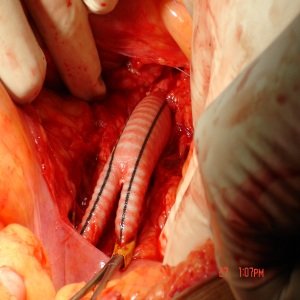

Leg Bypass To Prevent Amputation

When there is long segment blockage of leg arteries, leg bypass surgery is performed to improve the blood flow and prevent amputation. A properly trained and dedicated vascular specialist can perform this surgery at multiple levels from the abdomen (tummy) down to the foot.